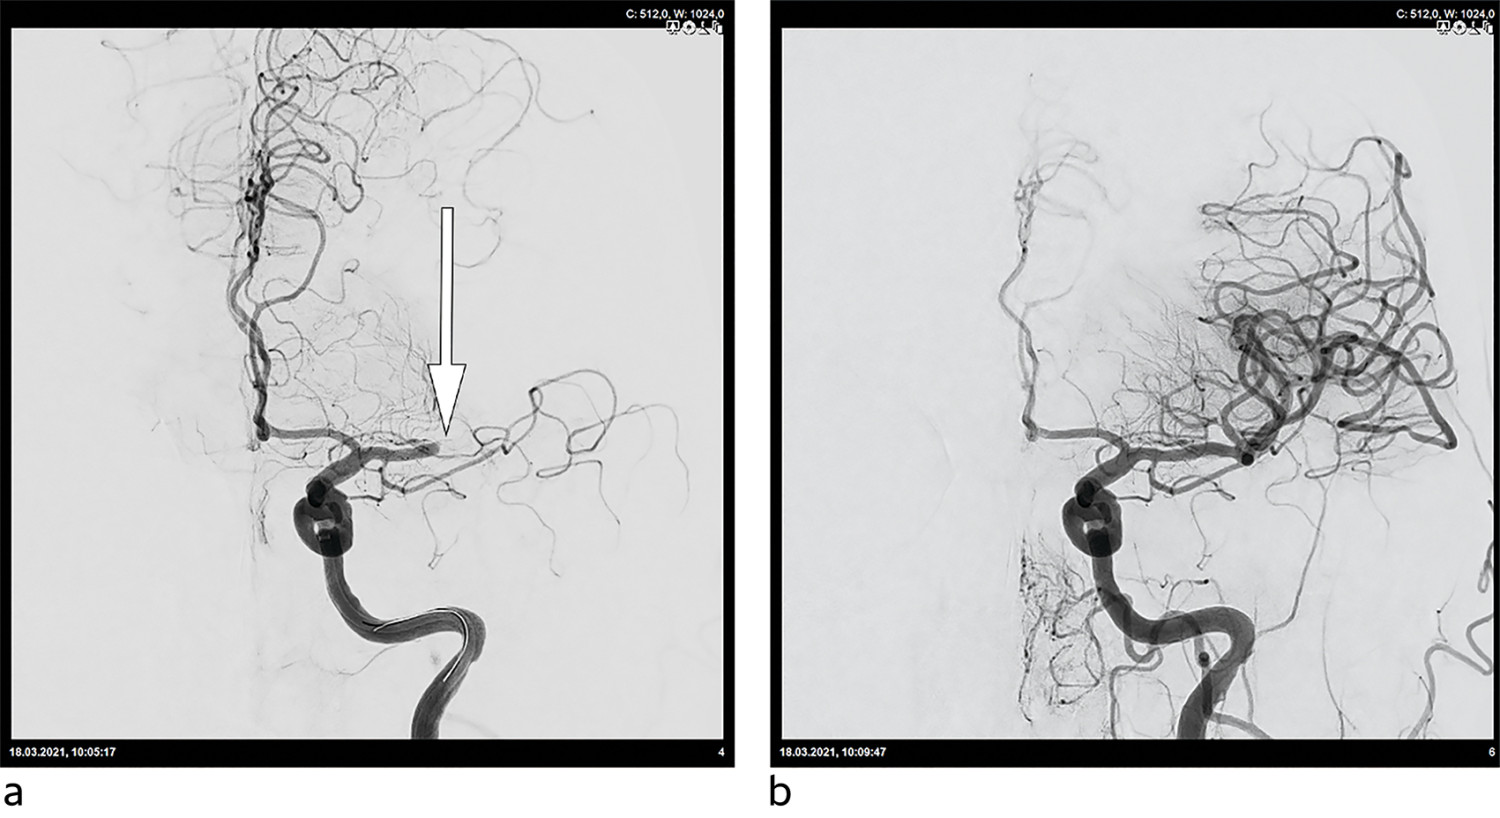

Trombektomi skal alltid vurderes ved akutt storkarokklusjon (figur 1). De fleste okklusjoner er lokalisert i arteria carotis interna eller i første segment av a. cerebri media (figur 2). Tandemokklusjoner utgjør rundt 15 % av alle hjerneinfarkt i det fremre cerebrale kretsløpet (14, 15). De fleste pasienter får intravenøs trombolytisk behandling før trombektomi. Direkte trombektomi uten trombolytisk behandling kan være å foretrekke hvis pasienten legges direkte inn på et trombektomisenter (16).